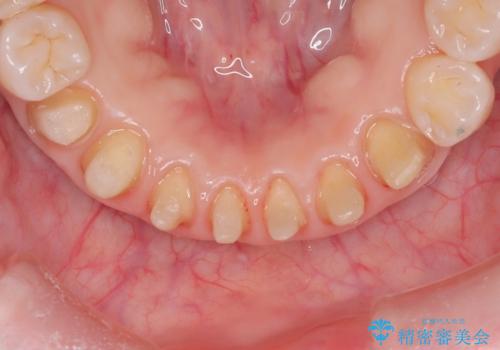

【オールセラミック】下の前歯が痛い。

- 以前に治療した前歯が痛むことを主訴に来院されました。

根っこに病気があり、根管治療から被せ物まで治療を行いました。

根管治療を行った後、3ヶ月間治癒の確認をしてからオールセラミックスペシャルで治療を行いました。